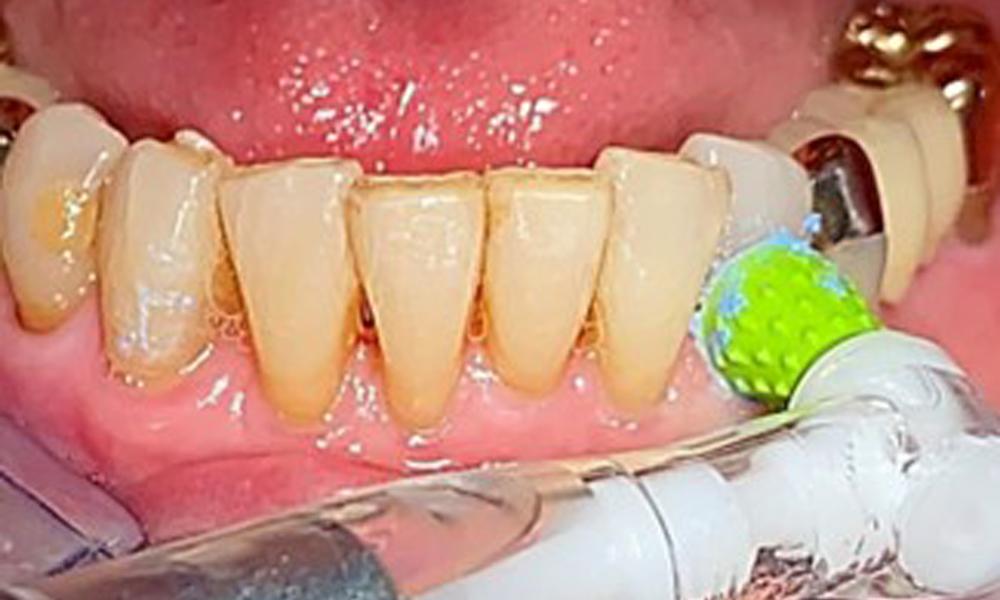

Selective polishing of tooth 33 (Proxeo Twist, W&H, shown here)

Fig. 13: Selective polishing of tooth 33 (Proxeo Twist, W&H, shown here)

An air polishing system should be used with low-abrasive powder to remove biofilm from the restoration margins, interdental areas and implant surfaces (Fig. 12). Selective polishing (Fig. 13) should be used to smooth any less sensitive areas, as this decreases bacterial reattachment (9).